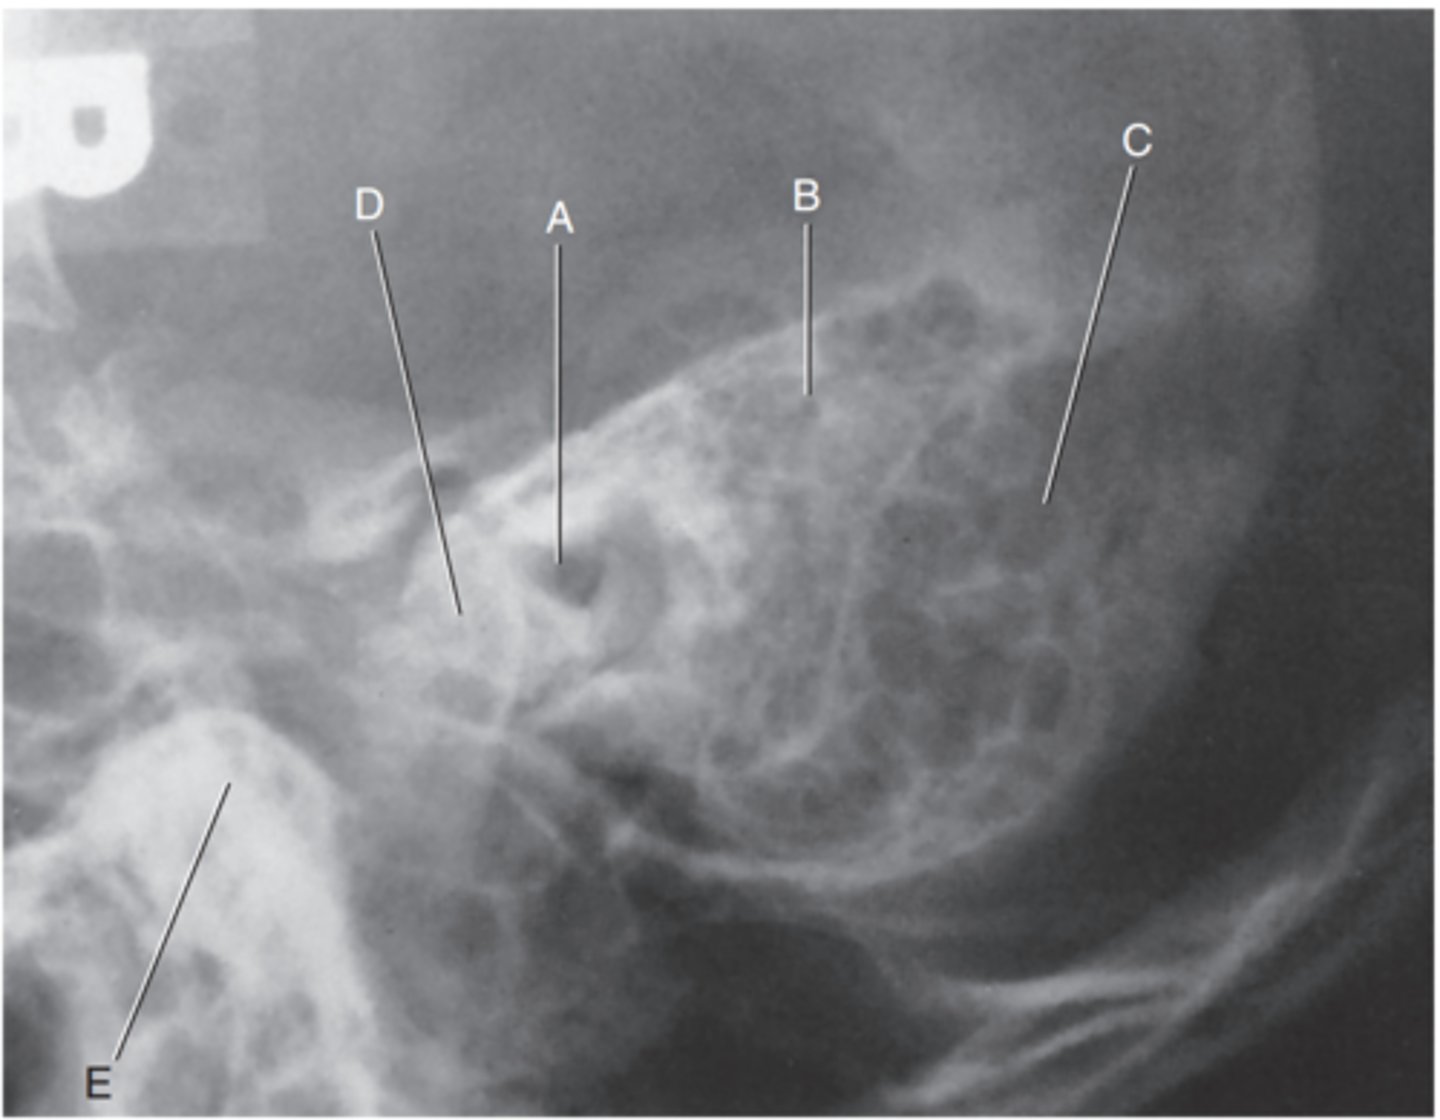

Petrous ridge

Label A

Bony (osseous) labyrinth (semicircular canals)

Label B

EAM

Label C

Region of internal acoustic canal

Label D